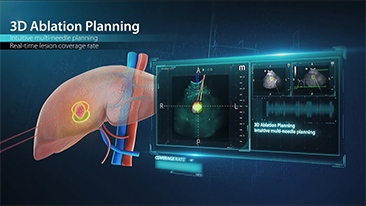

??? ?? ??? ?? ???? ? ??? ?? ??? ?? ??? ??? ??? ???. ???? ??? UWN+ ?? ?? ??? ?? MI??? ??? ??? ?? ?? ??? ?? ?? ?? ???, ?? ?? ?? ???? ??? ? ????.